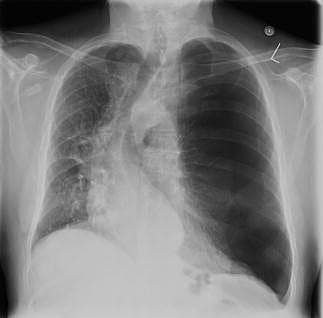

En 64-årig mand vågnede med åndenød og en skarp smerte tværs over brystet natten efter en glad aften i Cirkusrevyen. Patienten var læbecyanotisk, dyspnøisk og havde forlænget expirium. Ved ankomsten til sygehuset var saturationen 90% uden ilt, og blodtrykket var 190/90 mmHg. Et elektrokardiogram viste sinustakykardi med frekvens 103. Der blev fundet høje »pulmonale« p-takker, men normal hjerteakse. Der var ingen tegn på iskæmi eller belastning. Ved stetoskopi var der fravær af respirationslyd på venstre thoraxhalvdel og nedsat thoraxbevægelighed. Ved en røntgenundersøgelse af thorax afslørede man en stor pneumothorax på venstre side, hvilket medførte svær deviation af cor og øvrige midtlinjestrukturer. Patienten blev behandlet med akut pleuradrænanlæggelse.